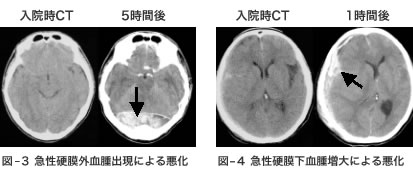

CTスキャンで血腫(けっしゅ)の出現や増大が原因と診断されれば、緊急開頭手術が必要になります。急性硬膜外血腫(図-3)では回復が期待できますが、急性硬膜下血腫(図-4)や脳挫傷・脳内血腫の増悪例では救命すら困難な場合があります。一見大丈夫と思われても重症化することがあるということです。

CT画像:周囲の白いリング状部分が頭蓋骨、灰色部分が脳、黒矢印先の白色(+灰色)部分が血腫です。